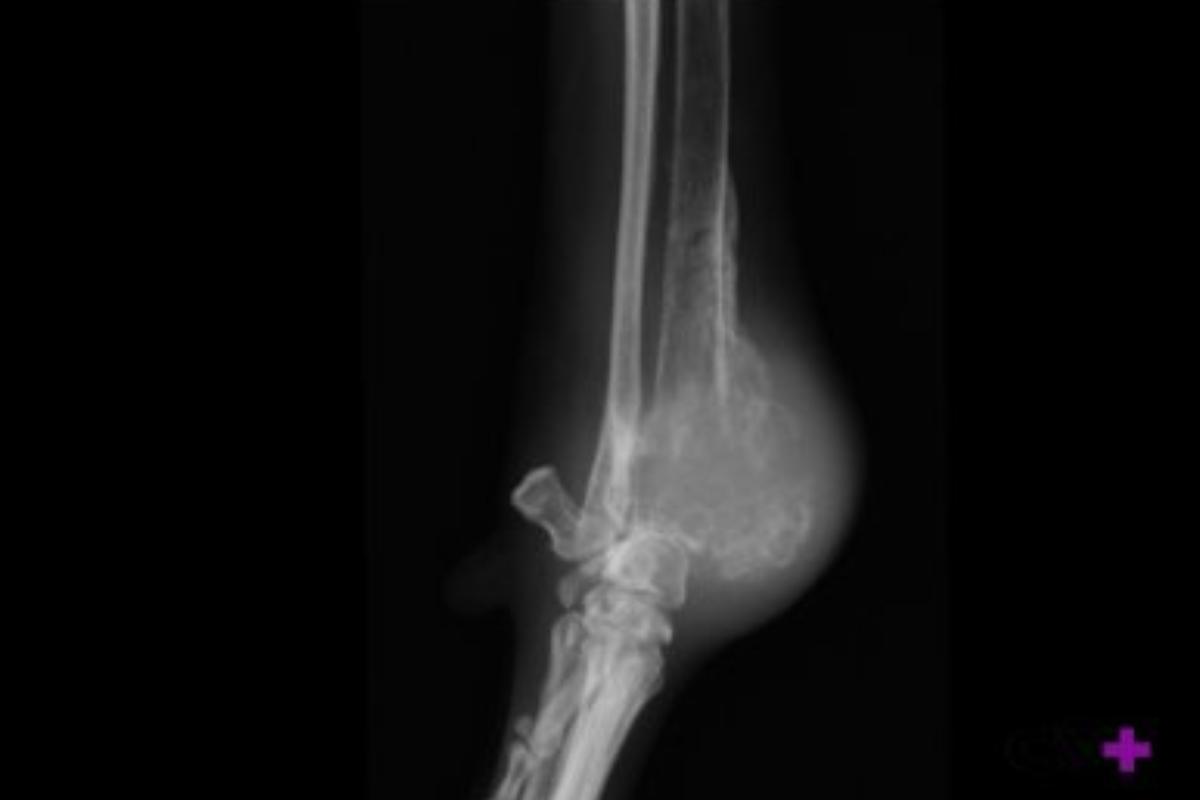

- Radiografia: lesões com margens irregulares e mal definidas, especialmente quando aparecem nos locais mais frequentes deste tumor, nos fazem suspeitar da existência do osteossarcoma canino. Além disso, as fraturas podem às vezes ser vistas na radiografia, pois uma pequena porcentagem de cães com osteossarcoma pode ter fraturas patológicas, ou seja, fraturas resultantes de danos ósseos causados pelo tumor. Vale mencionar que os exames de imagem permitem um diagnóstico presuntivo, mas para se chegar a um diagnóstico definitivo são necessários os seguintes exames:

- No caso do membro dianteiro: longe do cotovelo, ou seja, no úmero proximal ou no raio distal.

- No caso dos membros posteriores: perto do joelho, ou seja, no fêmur distal ou na tíbia proximal.